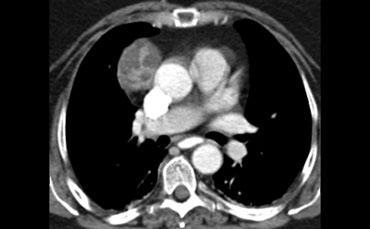

Trước khi tiến hành sinh thiết một khối trung thất trước, cần lưu ý rằng một số tổn thương này có thể có nguồn gốc mạch máu.

CT cho thấy một khối trung thất trước có tỷ trọng tương đương nước.

Đây là hình ảnh điển hình của nang tuyến ức.

Hãy mô tả hình ảnh bên trái.

Sau đó tiếp tục.

CT cho thấy một khối nằm ở trung thất trước.

Khối có dạng nang nhưng có các vách ngăm thuốc cản quang dạng đặc.

Đây là dấu hiệu rất đặc trưng của u tế bào mầm.

Nhiều người cho rằng u tế bào mầm phải chứa mỡ và nếu tổn thương không chứa mỡ thì không thể là u tế bào mầm.

Cần nhớ rằng chỉ khoảng 60% u tế bào mầm có chứa mỡ, do đó sự vắng mặt của mỡ không loại trừ u tế bào mầm khỏi chẩn đoán phân biệt.

Thành phần đặc càng nhiều thì khả năng u tế bào mầm ác tính càng cao.

Khối có dạng nang nhưng có các thành phần đặc ngấm thuốc cản quang, do đó cần lo ngại đến u lympho, u tế bào mầm và u tuyến ức dạng nang.

Trường hợp này được xác định là u tuyến ức dạng nang.